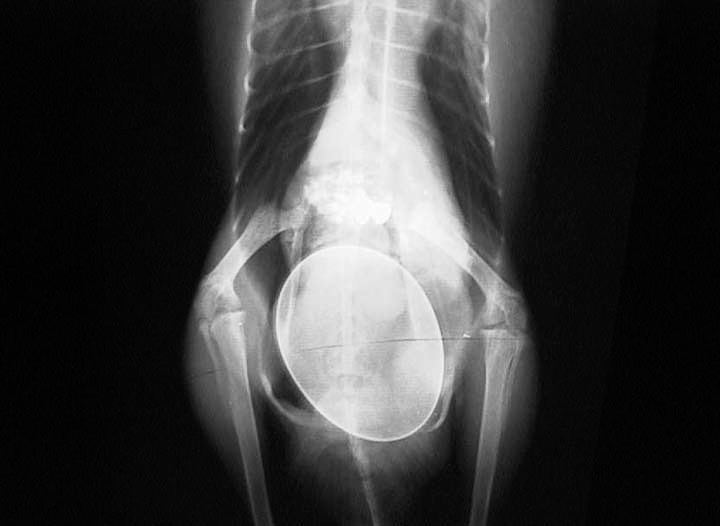

Kiwi Bird X Ray Egg . Genus apteryx) are famous for laying an enormous egg in comparison with their relatively small body size. Most strikingly, without needing to. According to the audubon society, a kiwi egg can can. By comparison, the kiwi egg takes up about 20% of the mother’s body. From most extreme animals on animal planet, footage of a kiwi laying an egg, complete. Genus apteryx) are famous for laying an enormous egg in comparison with their relatively small body size. Unlike flying birds, kiwis have relaxed constraints on their weight, and this is reflected in aspects of their anatomy such as their more solid bones.

Genus apteryx) are famous for laying an enormous egg in comparison with their relatively small body size. Unlike flying birds, kiwis have relaxed constraints on their weight, and this is reflected in aspects of their anatomy such as their more solid bones. From most extreme animals on animal planet, footage of a kiwi laying an egg, complete. Most strikingly, without needing to. Genus apteryx) are famous for laying an enormous egg in comparison with their relatively small body size. According to the audubon society, a kiwi egg can can. By comparison, the kiwi egg takes up about 20% of the mother’s body.

Kiwi Bird X Ray Egg Most strikingly, without needing to. By comparison, the kiwi egg takes up about 20% of the mother’s body. According to the audubon society, a kiwi egg can can. Unlike flying birds, kiwis have relaxed constraints on their weight, and this is reflected in aspects of their anatomy such as their more solid bones. From most extreme animals on animal planet, footage of a kiwi laying an egg, complete. Genus apteryx) are famous for laying an enormous egg in comparison with their relatively small body size. Genus apteryx) are famous for laying an enormous egg in comparison with their relatively small body size. Most strikingly, without needing to.

Kiwi skeleton with the egg inside (yes this is real)https//ift.tt Kiwi Bird X Ray Egg Genus apteryx) are famous for laying an enormous egg in comparison with their relatively small body size. According to the audubon society, a kiwi egg can can. From most extreme animals on animal planet, footage of a kiwi laying an egg, complete. Genus apteryx) are famous for laying an enormous egg in comparison with their relatively small body size. By. Kiwi Bird X Ray Egg.

Kiwi Xray shows the huge size of her egg Anatomy To You Kiwi Bird X Ray Egg From most extreme animals on animal planet, footage of a kiwi laying an egg, complete. Genus apteryx) are famous for laying an enormous egg in comparison with their relatively small body size. Unlike flying birds, kiwis have relaxed constraints on their weight, and this is reflected in aspects of their anatomy such as their more solid bones. Genus apteryx) are. Kiwi Bird X Ray Egg.

XRay of a kiwi bird with its egg r/BeAmazed Kiwi Bird X Ray Egg Most strikingly, without needing to. From most extreme animals on animal planet, footage of a kiwi laying an egg, complete. By comparison, the kiwi egg takes up about 20% of the mother’s body. Unlike flying birds, kiwis have relaxed constraints on their weight, and this is reflected in aspects of their anatomy such as their more solid bones. According to. Kiwi Bird X Ray Egg.

Xray showing size of kiwi egg in female Rayon X, Pregnant Cat, Bird Kiwi Bird X Ray Egg From most extreme animals on animal planet, footage of a kiwi laying an egg, complete. Genus apteryx) are famous for laying an enormous egg in comparison with their relatively small body size. According to the audubon society, a kiwi egg can can. Most strikingly, without needing to. By comparison, the kiwi egg takes up about 20% of the mother’s body.. Kiwi Bird X Ray Egg.